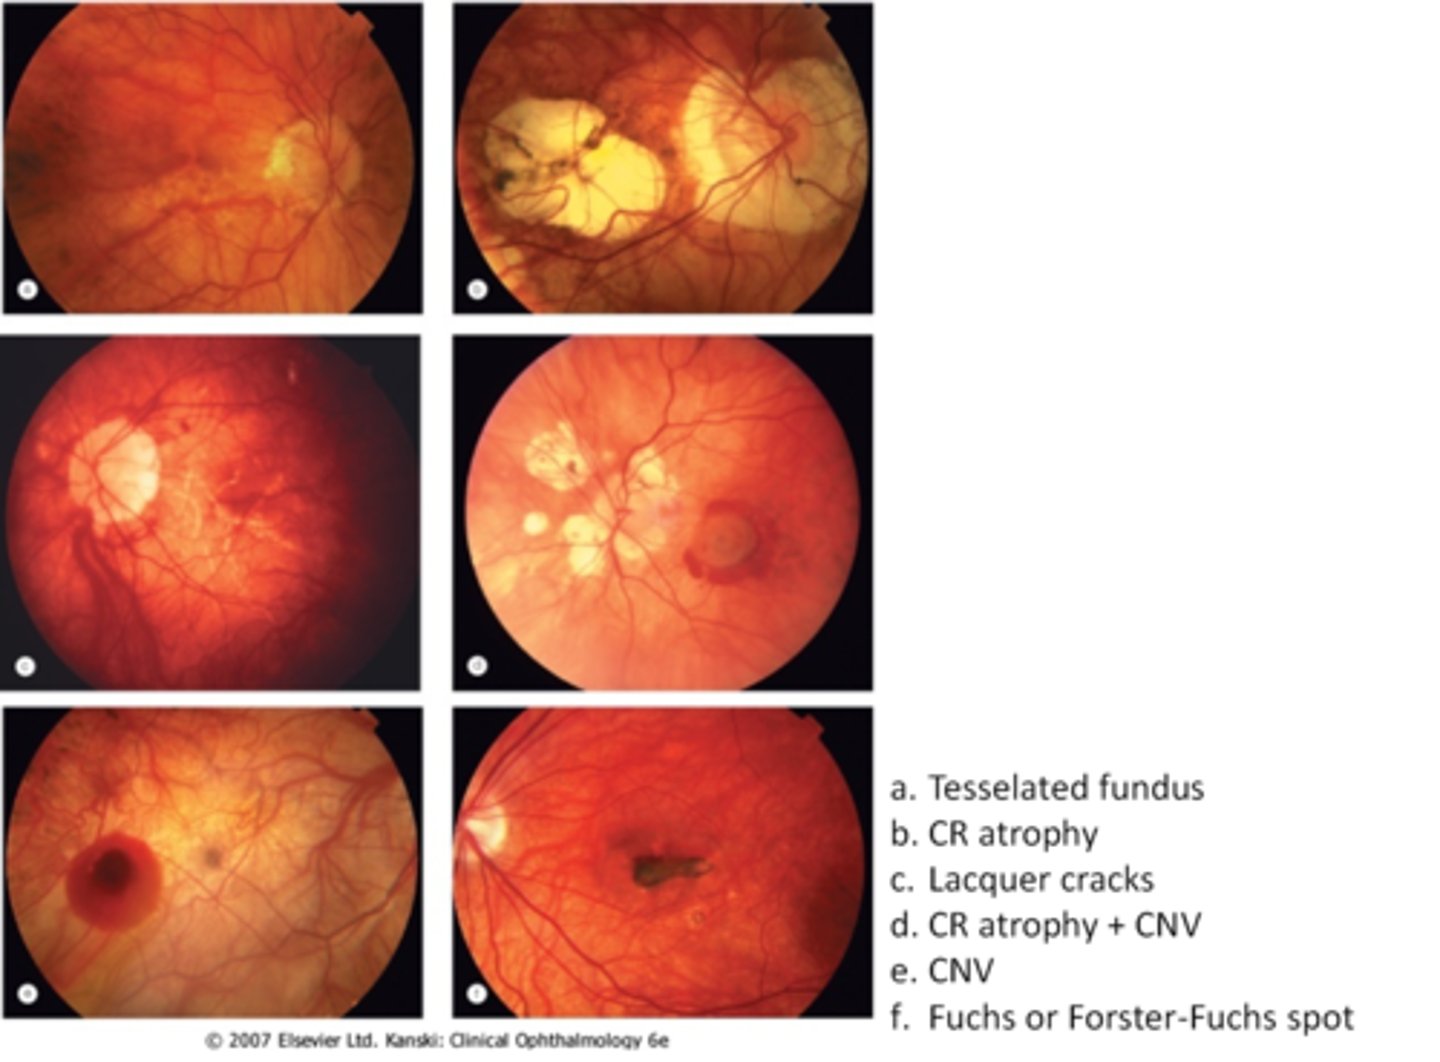

What finding of toxoplasmosis is seen in A/B?

retinitis turns into hazy scar with nerve pallor

What finding of toxoplasmosis is seen in C/D?

scarring overtime with VA loss/scotoma

What is seen in toxoplasmosis with OCT?

acute = retinitis = inflam, thickening of layers

acute = vitritis = dots and haze vitreous

chronic = necrotizing atrophy = scarring, thinning

What findings of toxoplasmosis are seen here?

retinal vasculitis

exudative scar

focal, hazy vitritis and retinitis

What findings of toxoplasmosis are seen here?

latent scars